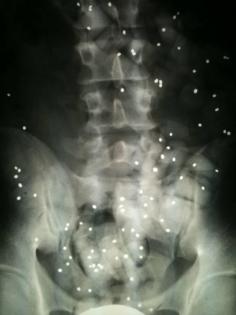

The intervertebral disks do not have their own blood supply which means that the get supplied with nutrients when you move. You can compare an intervertebral disk with a pin. If you swage the pin, twist it and bend it over the pin will break very fast. Same applies for the intervertebral disks which will get damaged if you lift a heavy case from your car with a rotary movement.

Most often it will be the best to test as many possible ways as possible. There are only a few movements which could be harmful. You can compare an intervertebral disk with a pin. If you swage the pin, twist it and bend it over the pin will break very fast. Same applies for the intervertebral disks which will get damaged if you lift a heavy case from your car with a rotary movement. This is maybe the only movement which could be really harmful.

Due to the fact that the vertebral column and its disks can be seen as a mechanical element we can once more compare it to a pin.

Heavy loads should be lifted proximally otherwise there would be too much weight force acting on the frontal part of the intervertebral disks. If you try to twist the disk in addition the disk would not be able to withstand this forces which also applies for a pin.